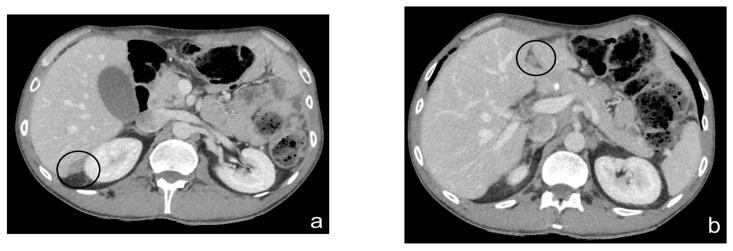

Peritoneal carcinosis is a condition characterized by the spread of cancer cells to the peritoneum, which is the thin membrane that lines the abdominal cavity. It is a serious condition that can result from many different types of cancer, including ovarian, colon, stomach, pancreatic, and appendix cancer. The diagnosis and quantification of lesions in peritoneal carcinosis are critical in the management of patients with the condition, and imaging plays a central role in this process. Radiologists play a vital role in the multidisciplinary management of patients with peritoneal carcinosis. They need to have a thorough understanding of the pathophysiology of the condition, the underlying neoplasms, and the typical imaging findings. In addition, they need to be aware of the differential diagnoses and the advantages and disadvantages of the various imaging methods available. Imaging plays a central role in the diagnosis and quantification of lesions, and radiologists play a critical role in this process. Ultrasound, computed tomography, magnetic resonance, and PET/CT scans are used to diagnose peritoneal carcinosis. Each imaging procedure has advantages and disadvantages, and particular imaging techniques are recommended based on patient conditions. Our aim is to provide knowledge to radiologists regarding appropriate techniques, imaging findings, differential diagnoses, and treatment options. With the advent of AI in oncology, the future of precision medicine appears promising, and the interconnection between structured reporting and AI is likely to improve diagnostic accuracy and treatment outcomes for patients with peritoneal carcinosis.

腹膜癌是一种以癌细胞扩散至腹膜为特征的病症,腹膜是衬于腹腔的一层薄膜。它是一种严重的病症,可由多种不同类型的癌症引发,包括卵巢癌、结肠癌、胃癌、胰腺癌和阑尾癌。腹膜癌中病变的诊断和定量对于该病症患者的管理至关重要,而影像学在这一过程中发挥着核心作用。放射科医生在腹膜癌患者的多学科管理中起着至关重要的作用。他们需要对该病症的病理生理学、潜在肿瘤以及典型的影像学表现有透彻的了解。此外,他们需要知晓鉴别诊断以及各种可用影像学方法的优缺点。影像学在病变的诊断和定量中起着核心作用,放射科医生在这一过程中起着关键作用。超声、计算机断层扫描、磁共振成像和正电子发射断层显像/计算机断层扫描(PET/CT)用于诊断腹膜癌。每种成像检查都有其优缺点,会根据患者情况推荐特定的成像技术。我们的目的是向放射科医生提供有关合适技术、影像学表现、鉴别诊断和治疗方案的知识。随着人工智能在肿瘤学中的出现,精准医学的未来似乎很有前景,结构化报告与人工智能之间的相互联系可能会提高腹膜癌患者的诊断准确性和治疗效果。